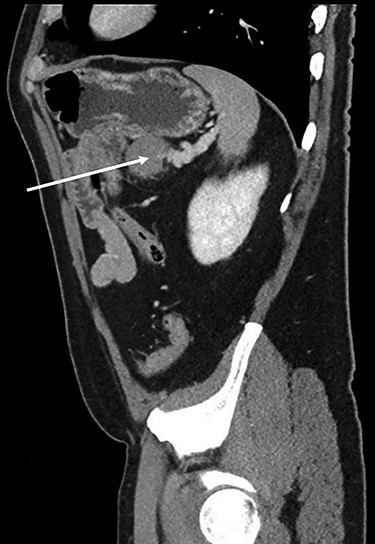

Abdominopelvic CT scan disclosed a 3.7-cm mass, between the tail of the pancreas and the splenic hilum, causing a narrowing of the splenic vein and splenomegaly (Figs 1–3).

Sagital CT scan of abdomen, selected image from a pancreatic protocol, late arterial/pancreatic phase. A 3.7-cm mass, between the tail of the pancreas and the splenic hilum, causing a narrowing of the splenic vein and splenomegaly (arrow).